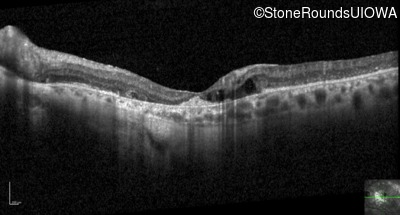

Optical Coherence Tomography - Left - 20/80

Exemplar / OCT Stack